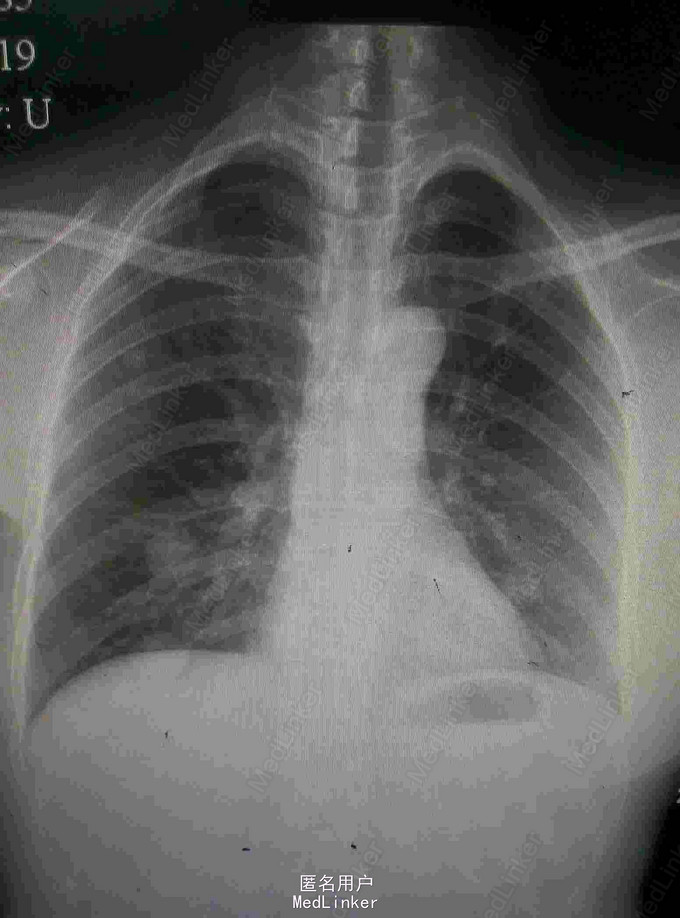

患者,女,51岁,右乳癌术后10月余,出现双肺转移1周 患者原发肿物位于右乳12点距离乳头2cm,大小约1.9*1.6cm,于2014-9-25行右乳癌改良根治术+前哨淋巴结活检术,术后病理示:RIDC,III级,ER(-)、PR(-)、HER-2(-)、Ki-67(+,70%),术后行EC*4-T*4化疗.

2015-08-19:我院胸片和CT示双肺多发结界影考虑转移瘤

诊断:右乳癌术后伴双肺转移 治疗:入院行骨扫描检查未发现转移,行GX方案姑息性辅助化疗